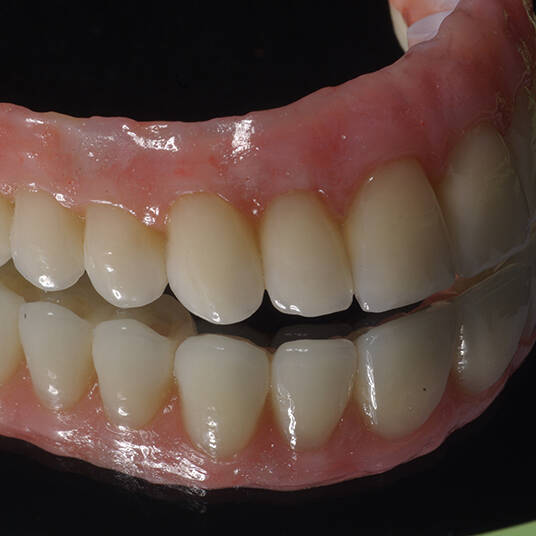

Utilizamos a tecnologia CAD CAM, um sistema avançado que possibilita a confecção precisa das próteses dentárias diretamente sobre os implantes. Esse método inovador garante um ajuste perfeito, um resultado estético superior e proporciona muito mais conforto e durabilidade. Com o CAD CAM, nossos pacientes contam com um processo mais rápido e previsível para alcançar o sorriso desejado.

Nosso compromisso é oferecer um tratamento de excelência, com profissionais especializados e tecnologia de última geração para implantes dentários em Fortaleza. Venha nos visitar e descubra por que a Clínica Pontes Odontologia é referência em implantes dentários em Fortaleza, devolvendo sorrisos e qualidade de vida aos nossos pacientes.